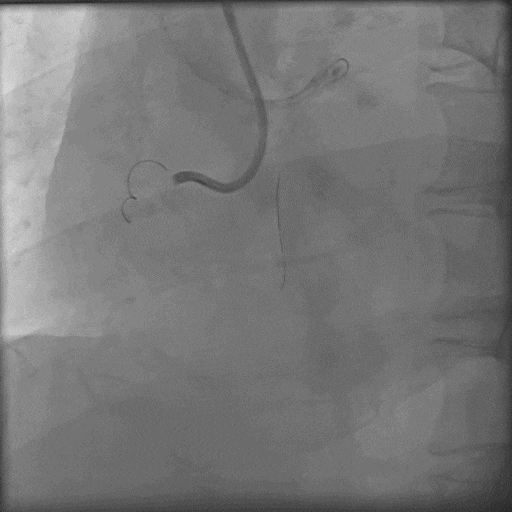

预案正向找到血管结构,ADR术式可快速高效开通右冠CTO,即使走逆向,也得进行充分正向准备,以进行Reverse-Cart;选择7F-AL1强支撑指引导管,由于近端纤维帽坚硬, Gaia3导丝、P200导丝前向试探失败;XTA、P200导丝Knuckle失败;

导丝怎么扩秦川论剑|张勇:攻坚克难——解决器械难以通过的CTO病变之技术图谱_https://www.jmylbn.com_新闻资讯_第17张

导丝怎么扩秦川论剑|张勇:攻坚克难——解决器械难以通过的CTO病变之技术图谱_https://www.jmylbn.com_新闻资讯_第18张

Carlino后导丝仍无法前行;

导丝怎么扩秦川论剑|张勇:攻坚克难——解决器械难以通过的CTO病变之技术图谱_https://www.jmylbn.com_新闻资讯_第19张

3.0后扩球囊Base;